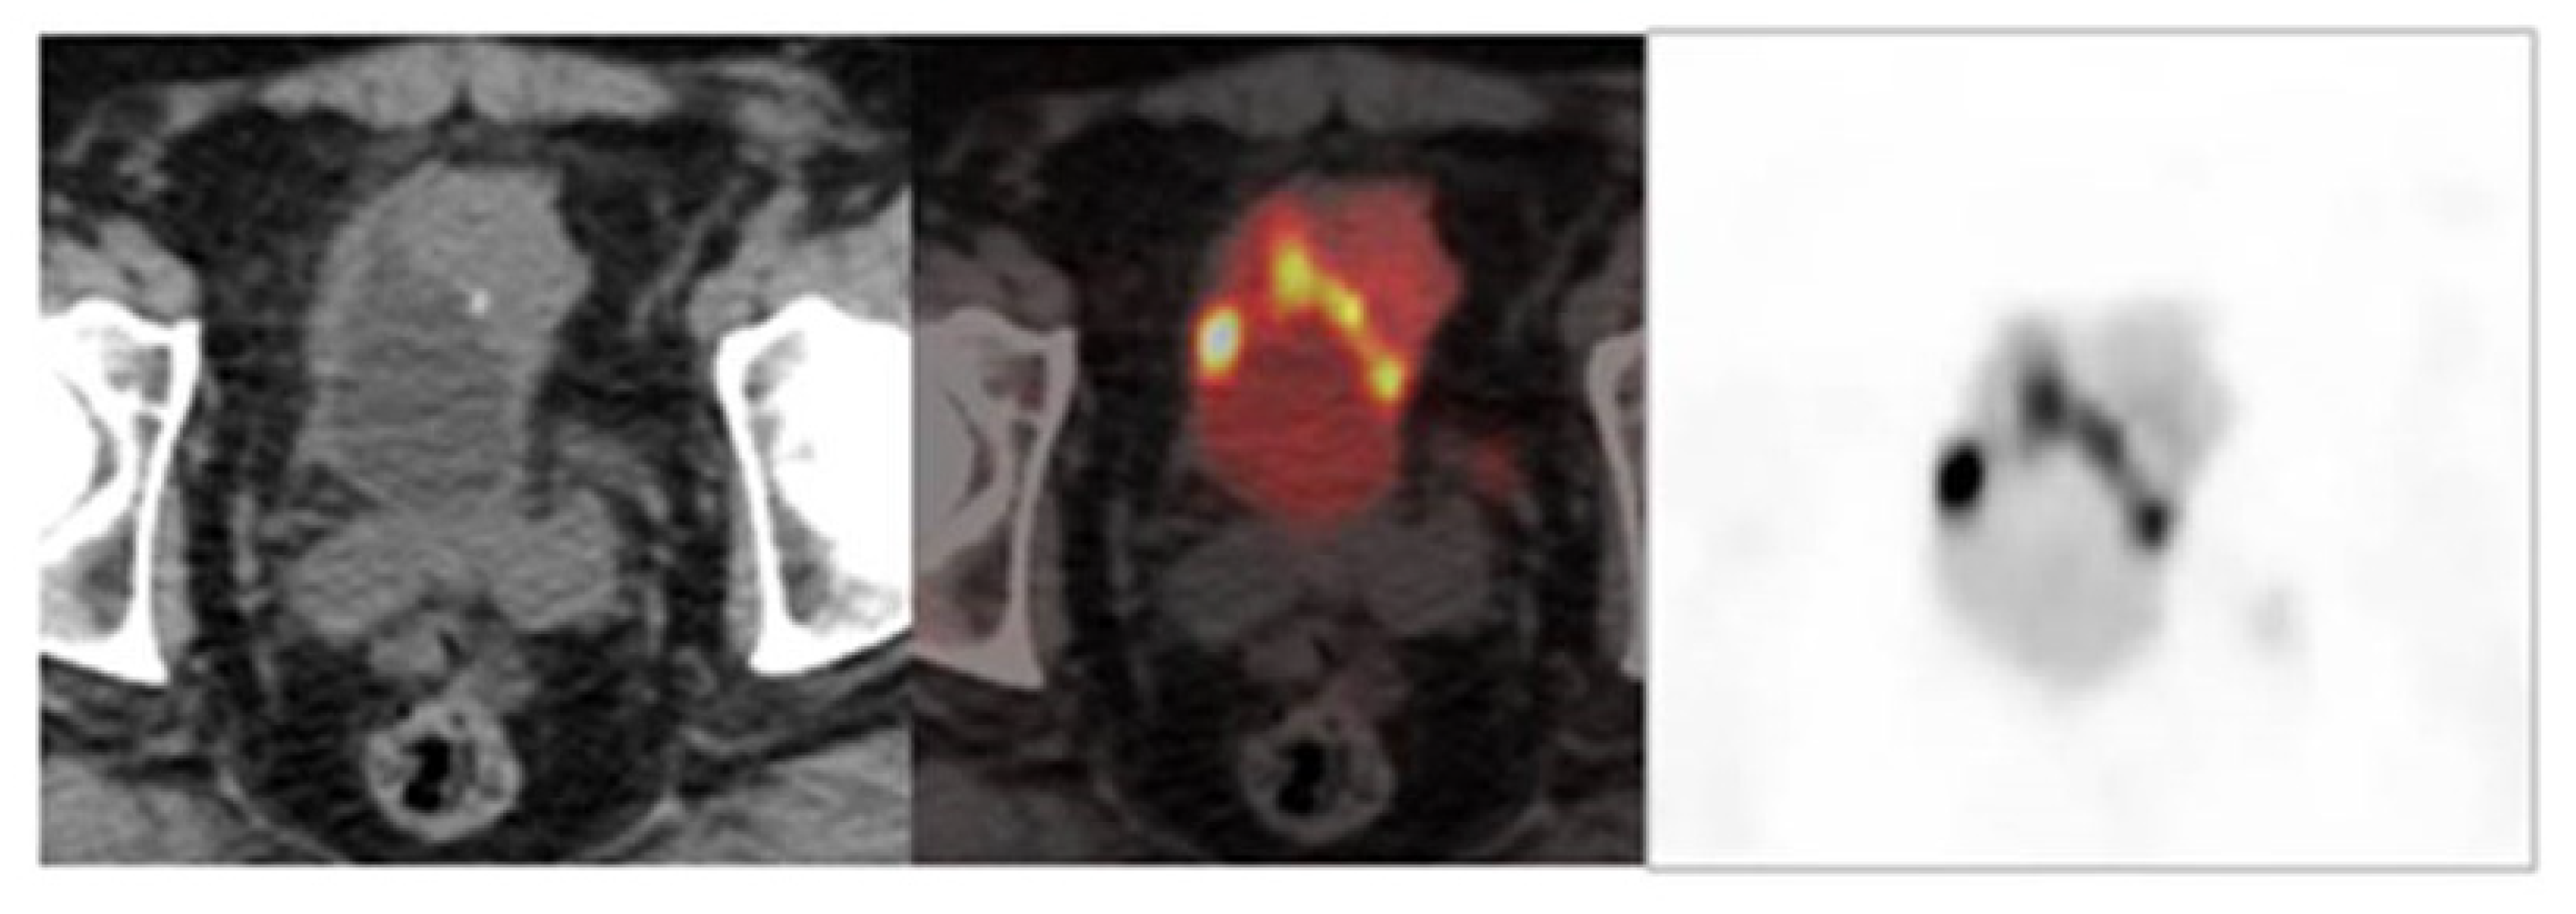

6.1. Nuclear Medicine

- Optimization of FDG-PET/CT reliability in staging of MIBC.

- Design of prospective studies aimed to compare the value of different radioimaging techniques in parallel, and to define the impact of FDG-PET/CT in the selection of patients.

- To determine which imaging technique is most effective for predicting response after neoadjuvant chemotherapy or a guide for endoscopic biopsy.

- To unify the methodology for acquisition and interpretation of FDG-PET/CT.

- To define predictive risk models in which FDG-PET/CT would have the highest reliability in the detection of recurrence.

- To perform prospective studies for the comparison in parallel of FDG-PET/CT with other techniques for detecting recurrence in intermediate/high-risk patients.